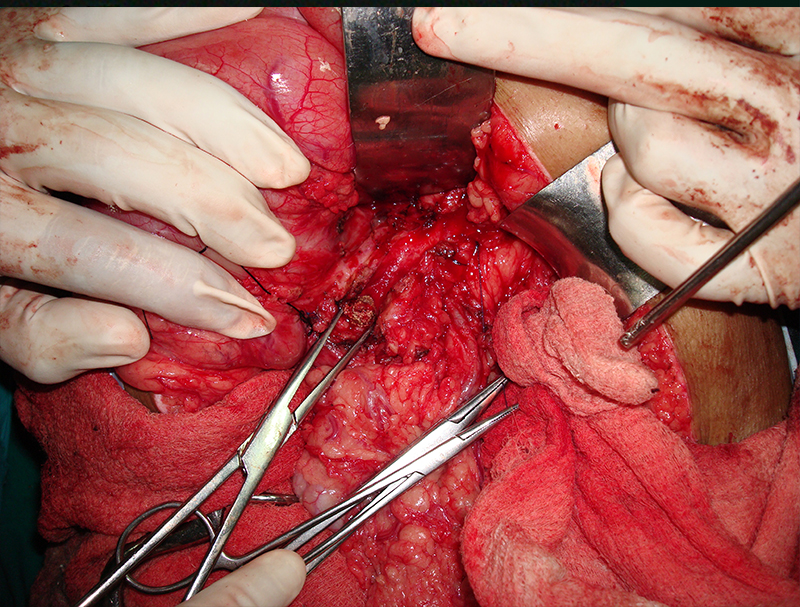

30 year old young lady with chronic pancreatitis, narrowing (stricture) of the pancreatic duct in the head and tail of pancreas and obstructing stone in the tail portion of the pancreatic duct presented to us with a recent attack of mild acute pancreatitis. She had undergone pancreatic duct stenting 3 times before this and stent migrated out of the duct at the last time following which she had acute pancreatitis. She was thoroughly evaluated with CT scan and MRI of abdomen. It showed that the duct had dilated irregularly in head and body of the pancreas and a stone was lodged in the tail. So she had disease both in the head and tail. She underwent a distal pancreatosplenectomy for the tail disease and a pancreaticojejunostomy (Head coring—Frey procedure) for the disease of the head and body of pancreas. She recovered well however the recovery was prolonged due to intra-abdominal infection caused by organisms in the infected pancreatic fluid. Infections originated from the pancreatic stents, were resistant to routine antibiotics and needed expensive drugs for infection control.

25 year old male presented with abdominal pain due to chronic calcific pancreatitis. He had had multiple previous endoscopic stent placement procedures & external shock wave treatment (ESWL) attempts to break & remove pancreatic stones and pancreatic duct stenting. He was investigated and later operated. A Frey procedure was done wherein the inflamed and stone filled core in the head of pancreas was removed, duct was widely opened along the head, neck, body and tail of pancreas. All the ductal stones were removed and multiple narrowing were opened. A loop of intestine was then joined with the pancreatic duct. He recovered uneventfully. He is fine for last 8 years and has not required any long term painkillers or had any episodes of pancreatitis. His dose of pancreatic enzyme supplements has also come down.

40 year old male with chronic calcific pancreatitis due to alcohol, continuous abdominal pain and weight loss underwent surgery (head coring and pancreaticojejunostomy). He did not have any previous stenting procedures. Patient recovered smoothly and was discharged on 6th day after surgery and has remained well for last 6 years.